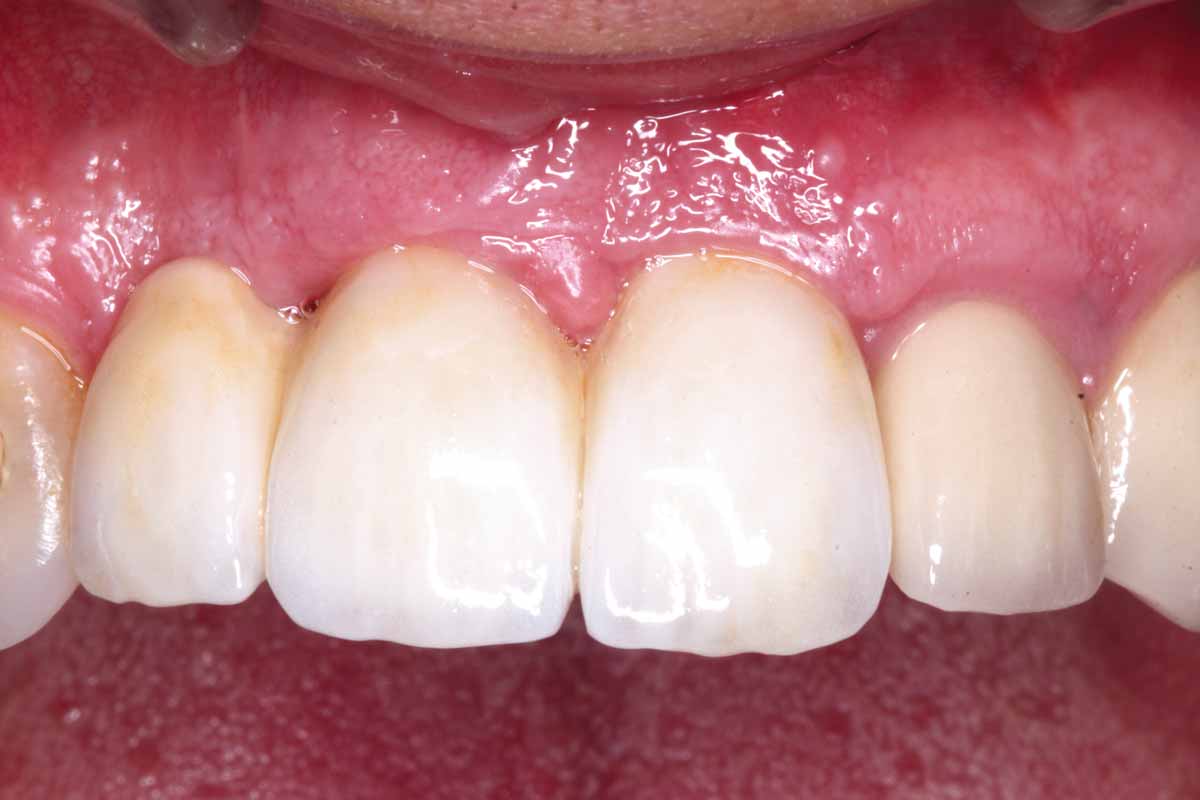

1/27 - Initial situation: missing teeth #11 & 12 and badly broken #21 root

GBR and soft tissue augmentation with cerabone® and mucoderm® - H. Maghaireh & V. Ivancheva